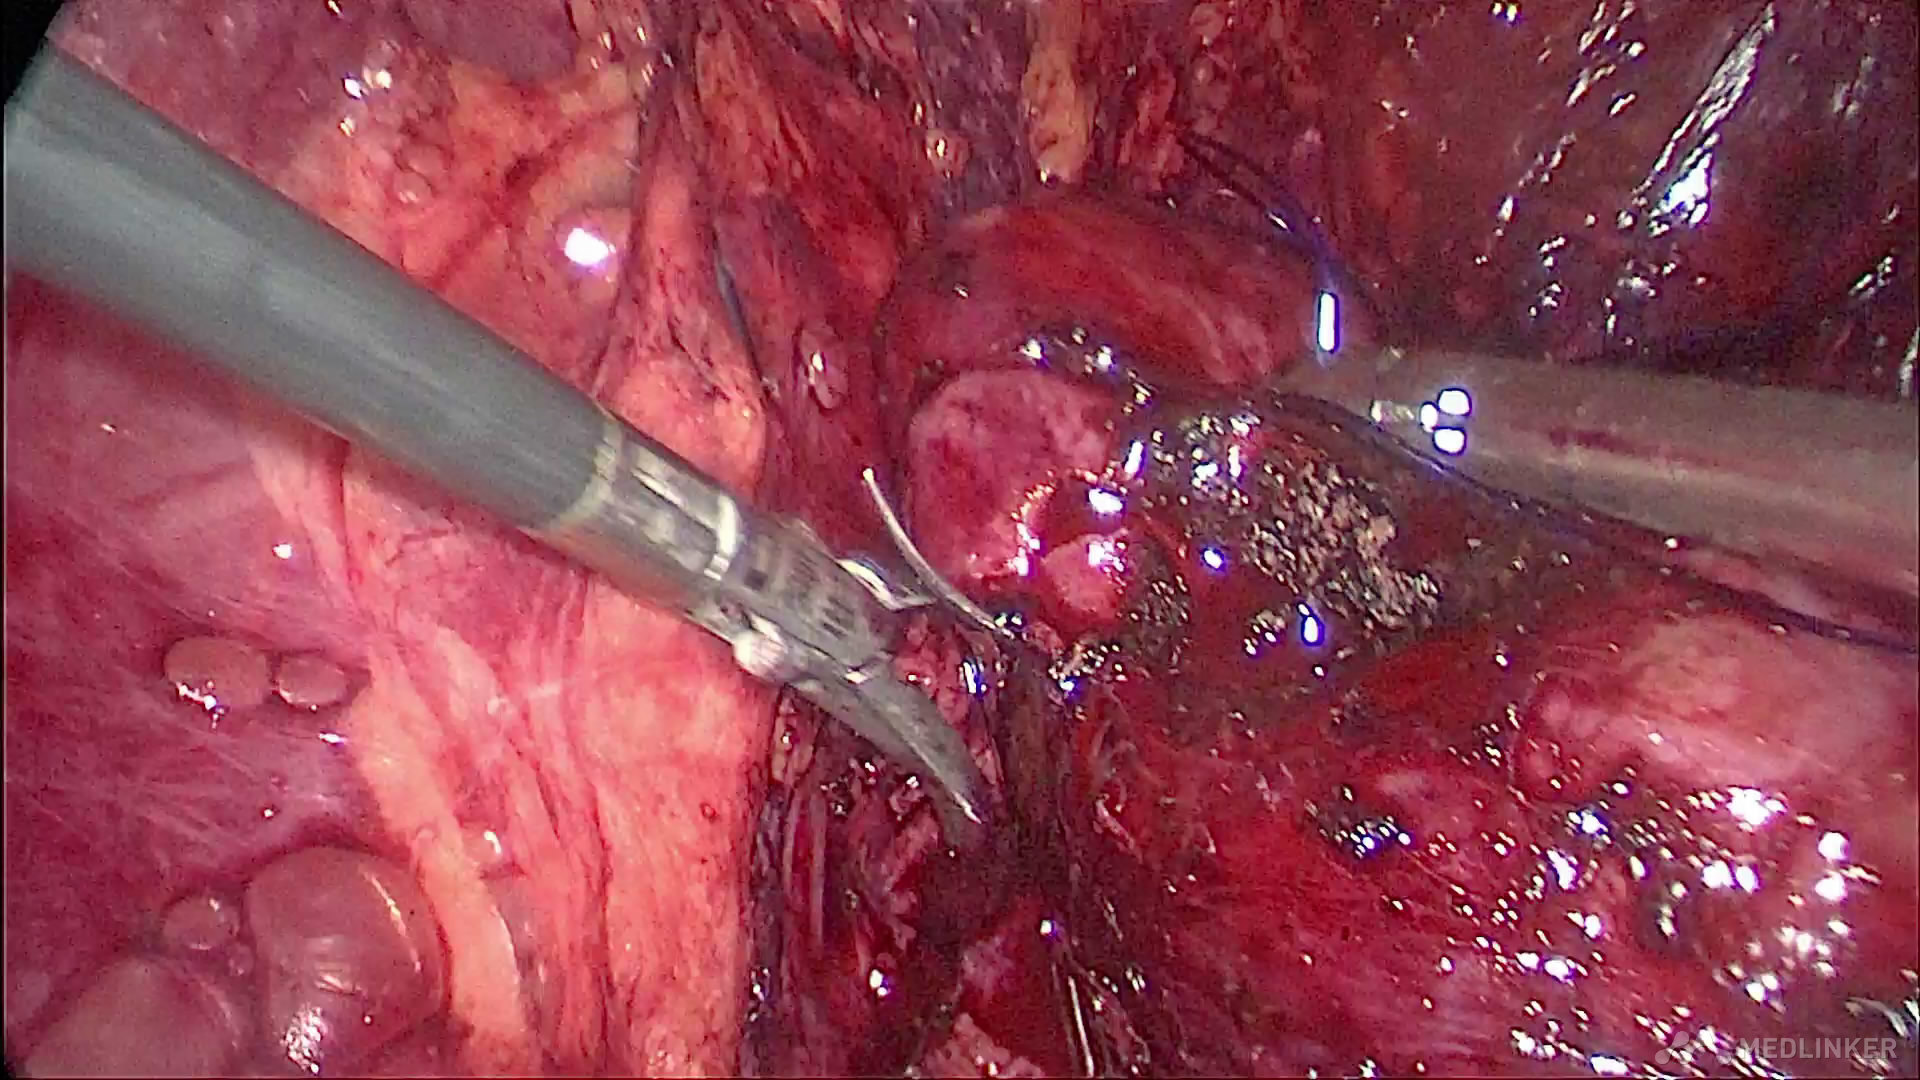

沿肿瘤包膜切除右肾肿瘤,在控制右肾动脉的情况下,创面出血不多,以渗血为主

完整切除肿瘤,发现肿瘤脂肪成分较多,快速病理提示符合右肾错构瘤改变

将深入肾实质的肿瘤切除,并仔细检查肾盂防止尿漏发生